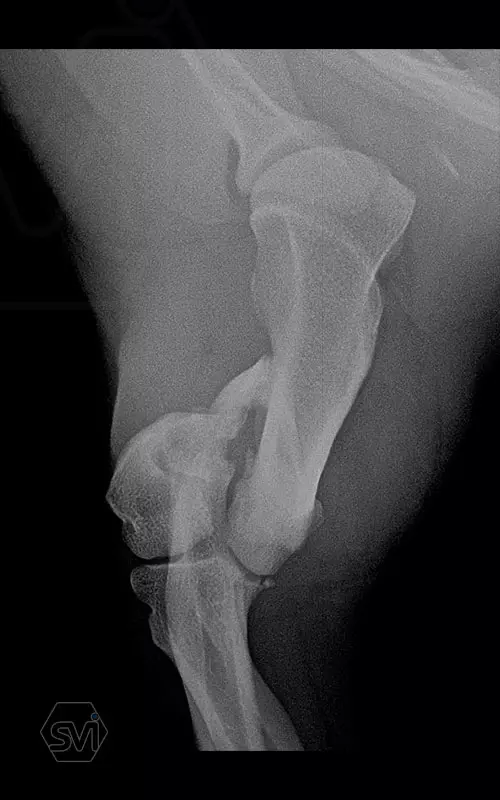

In our first case, we got right to the heart of it: we operated on a 2-year-old dachshund-type mixed dog weighing 9 kg, who overstretched his right humerus while stepping on pallets and suffered a Y-shaped humerus fracture that extended into the elbow joint combined with a large longitudinal splinter. To treat the fracture, we chose the new, cutable poliaxial locking plate, and immediately placed two, one medially and one caudolaterally. The intercondylar fracture and the longitudinal diaphysis fragment were each fixed with a 2.4 lag screw.